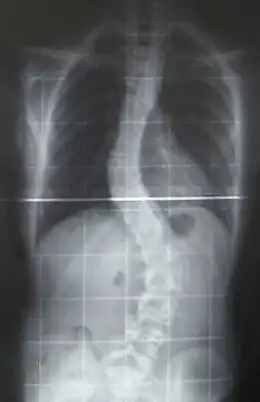

La scoliose est une déviation sinueuse de la colonne vertébrale dans les trois plans de l'espace : inclinaison dans le plan frontal, rotation des vertèbres dans le plan horizontal et inversion des courbures dans le plan sagittal. Il ne faut pas confondre la scoliose avec l'attitude scoliotique qui est une déviation dans un seul plan de l'espace, réductible et temporaire. La scoliose est une déformation permanente et irréductible. Une déviation du rachis est considérée comme une scoliose quand l'angulation est égale ou supérieure à 10 degrés.

Le principal critère d'évaluation de la scoliose est l'« angle de Cobb », qui se mesure sur une radiographie du rachis de face. C'est l'angle formé à partir de l'intersection de deux droites tangentielles l'une au plateau supérieur de la vertèbre limite supérieure, l'autre au plateau inférieur de la vertèbre limite inférieure. Les conventions médicales veulent qu'un angle inférieur à 10 degrés ne soit pas considéré comme une scoliose à part entière[35]. On peut classer les courbures scoliotiques en fonction de leur importance :